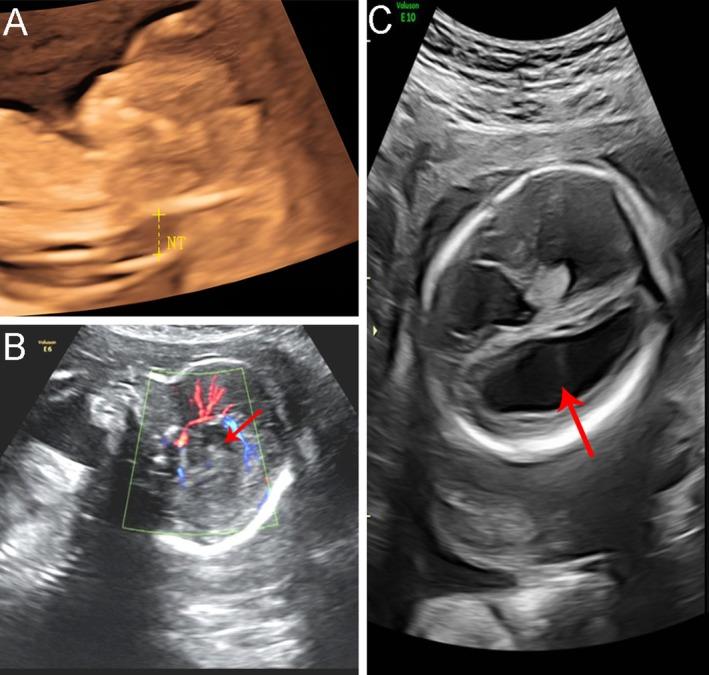

We describe a 28-year-old pregnant woman referred for increased nuchal translucency (4.4 mm) and high risk on first trimester screening. Noninvasive prenatal testing showed no common aneuploidies. At 23 weeks of gestation, fetal ultrasound revealed ventriculomegaly and suspected partial agenesis of the corpus callosum. Genetic testing included karyotyping, chromosomal microarray analysis (CMA), and trio-based whole exome sequencing (WES).

Karyotype and CMA were normal. WES identified a de novo heterozygous missense variant in PPP2R1A, NM_014225.6: c.548G>A (p.R183Q), classified as pathogenic. Following genetic counseling, the couple elected to terminate the pregnancy. Integrating our findings with 12 previously reported prenatal cases, we conducted a systematic review of fetal phenotypes associated with PPP2R1A variants. The most common features were ventriculomegaly (92%), agenesis or dysgenesis of the corpus callosum (50%), and congenital heart defects (42%).

方法

我们描述了一名28岁的孕妇,因颈项透明层增厚(4.4毫米)和孕早期筛查高风险而前来就诊。无创产前检测未发现常见的非整倍体。妊娠23周时,胎儿超声显示脑室扩大和疑似胼胝体部分发育不全。基因检测包括核型分析、染色体微阵列分析(CMA)和基于三联体的全外显子测序(WES)。

核型和CMA均正常。WES在PPP2R1A基因(NM_014225.6)中鉴定出一个新生的杂合错义变异,c.548G>A(p.R183Q),分类为致病性变异。经过遗传咨询,这对夫妇选择终止妊娠。将我们的发现与之前报道的12例产前病例相结合,我们对与PPP2R1A变异相关的胎儿表型进行了系统综述。最常见的特征是脑室扩大(92%)、胼胝体发育不全或发育异常(5